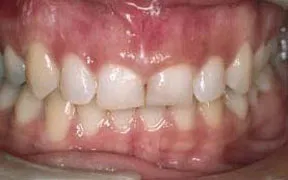

Periodontal Gallery Case 4

What is unusual about this case is the unevenness of the tissue height in the two front teeth.